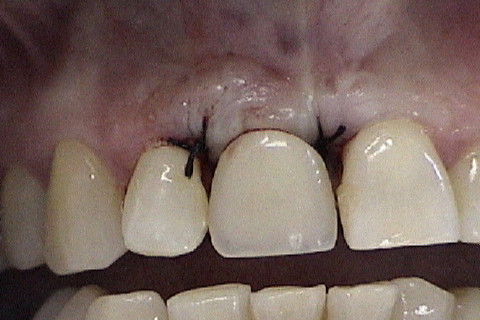

Vista vestibular da coroa metalo-ceramica

Aspecto da coroa metaloceramica no elemento 11

Paciente com fratura do elemento 11. Como havia grande perda óssea vestibular, optamos por fazer implante primeiramente a extração do dente e após 4 meses a colocação do implante. Concomitante 'a colocação do implante, enxerto óssseo + membrana para regeneração óssea foi colocado e aguardamos 6 meses para então fazermos a reabilitação com coroa metalo-ceramica parafusada.